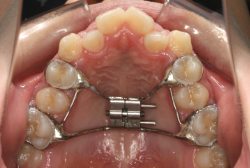

そこで、まず急速拡大装置を使用して上顎骨の拡大を行い、上顎骨の容量が拡大したことを確認後、マルチブラケット装置を使って全体の修正をする、と言う二段階の作戦をとることになりました。

この時期に使う急速拡大装置は、適切な診断に基づいて正しく使用することで確実に骨を大きくすることができます。拡大することで隙間が確保できるので、永久歯の抜歯を避けることができます。

急速拡大装置を1日1回装置の中央にある拡大ネジを、ご自身で回して頂くことで25日間くらいかけて、6mmほど拡大しました。拡大後は、上顎の前歯の隙間が広がっていることがお分かりいただけると思うのですが、土台の骨ごと広がるのでこのような隙間ができます。その後1年半くらいマルチブラケット装置を使用して、全体の修正を行いました。